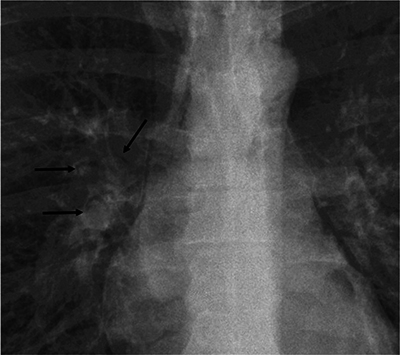

The air crescent (AC) is a common radiological sign. Even if its commonest aetiology remains pulmonary aspergillosis, various other causes have been described. In this study, we report four rare causes of ACs seen on chest radiographs that haven't been described in the literature. Teaching point: The differential diagnosis of an air crescent sign on chest radiographs includes oesophageal bezoar, interstitial lung emphysema, central bronchial stenosis and perforated emphysematous cholecystitis.

空气新月(AC)是一种常见的放射学征象。尽管其最常见的病因仍然是肺曲霉菌病,但也有其他各种病因的描述。在本研究中,我们报告了四种罕见的导致胸片上出现空气新月征的病因,这些病因在文献中还没有出现过。教学要点:胸片上出现气新月征的鉴别诊断包括食道大泡、肺间质气肿、中央支气管狭窄和穿孔性气肿性胆囊炎。